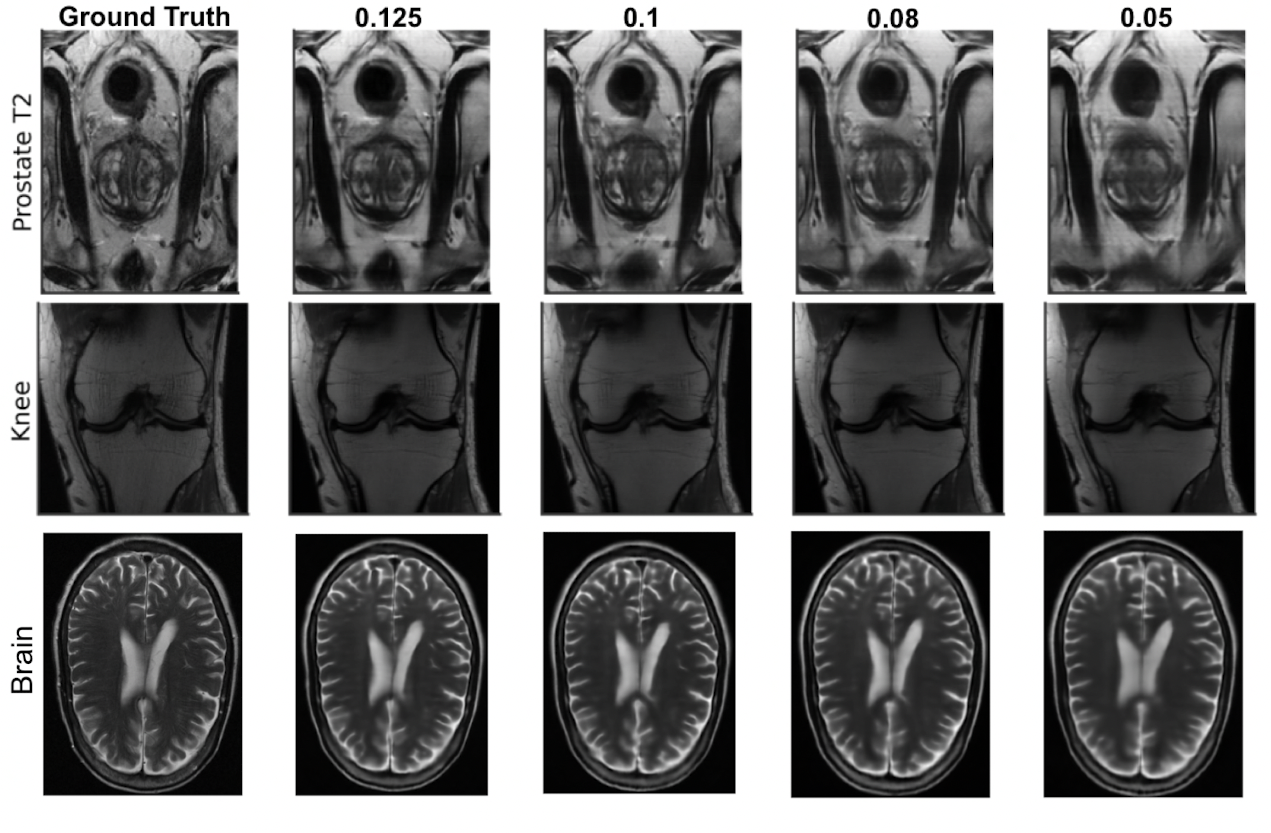

To understand the reason behind poor accessibility of mr, we first shed light on the workings of the pipeline. Figure 2 (c) depicts the full mr pipeline. mr imaging is an indirect imaging process in which the mr scanner subjects the human body with magnetic field and radio-frequency signals and measures the subsequent electromagnetic response activity from within the body. These measurements are collected in the Fourier space, also known as -space (see section in [7]) (stage S1 in figure 2 (c)). The D volumetric image of the anatomy is reconstructed from these k-space measurements using a multi-dimensional inverse Fourier transform (stage S2). The images are then finally interpreted by sub-specialized radiologists who render the final diagnosis (stage S3). The reason behind mr’s diagnostic success is its ability to generate these high-fidelity images with excellent soft-tissue contrast properties, because such images enable the human radiologists to easily discern the pathology accurately. The quality of the images is directly related to the quantity and the quality of the k-space measurements acquired: large quantities of high-quality measurements results in a high-quality image. This in-turn necessitates the need for 1) expensive specialized scanners installed in special purpose imaging centers to collect large quantities of high-quality k-space data, 2) execution of long and complex data acquisition protocols to reconstruct the high-fidelity images exhibiting multiple contrasts, and 3) sub-specialized radiologists to interpret the reconstructed images. All these factors prevent mr scanning to be used as a tool closer to poc for early and accurate disease identification. Instead its use is predominantly limited to validating a clinical hypothesis at the end of the diagnostic chain. With the motivation of improving accessibility of mr, researchers have proposed multiple solutions to simplify the pipeline. These include designing novel acquisition protocols to acquire the k-space data [32, 14], learning the under-sampling pattern over k-space data matrices so that the image quality is not compromised [2, 73, 64, 25], faster data acquisition and image reconstruction from the under-sampled k-space data, and for simultaneous classification and image-reconstruction using under-sampled k-space data [31, 39, 40, 70, 44, 20]. While these efforts have expedited the data acquisition process, the requirement to generate high-fidelity images still necessitates the use of expensive scanners and the need for a sub-specialized radiologist to interpret them. Furthermore, image generation also imposes limits on how much one can under-sample the -space. For instance, [44] reports that reconstructed images started missing clinically relevant pathologies if we sample less than of the data. This phenomenon can be observed in Figure 1, which shows images reconstructed by a state-of-the-art reconstruction model [56] using different levels of sampling. A clearly visible lesion in the high resolution image is barely visible in the image generated using data.

Figure 5 and table 3 give the auc, Sensitivity, and Specificity of the emrt model at different sampling rates and compares its performance to the model. We observe that at high sampling rates, the performance of emrt, in terms of auc and sensitivity-specificity, does not deteriorate significantly in comparison to the dl trained trained on high-fidelity images reconstructed using the full k-space data. This experiment demonstrates that if the goal is to simply infer the presence/absence of the disease, without the concern to reconstruct a high-fidelity image, then we can afford to significantly under-sample the k-space data (as low as %) without any significant loss in performance. This is in contrast to [44], which reports that in the Fastmri challenge, all submissions had reconstructed images that started missing clinically relevant pathologies at sampling rates less than of the data. Figure 1 shows the sequence of images reconstructed from the k-space data corresponding to the sampling patterns learnt by emrt. One can clearly see that the pathology visible is the image reconstructed from the full k-space is hard to discern in images generated from under-sampled data. Furthermore, it becomes successively hard to identify the pathology as we decrease the amount of data used.